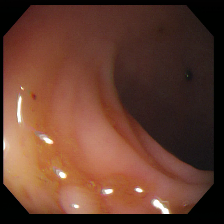

To show the effectiveness of our decoder consistency training approach, we compared our model with and without our consistency training approach. Table 2 shows the results of our model’s performance with and without consistency training. Using our consistency training approach, we are able to reduce false positive rates and improve the segmentation results for Kvasir-SEG [7], ClinicDB [1], ETIS [10], and EndoScene [13] datasets. Sample segmentation results as seen in Figure 2 also support these improvements.

Figure 2: Sample segmentation results of the benchmark models compared with PlutoNet without (Plu nC) and with consistency training (Plu wC). Images shown in the first column belong to Kvasir, ClinicDB, ColonDB, EndoScene, and Etis datasets.